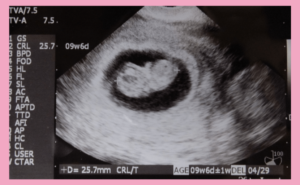

高齢出産で気を付けるべきこと:健康とリスク管理 2026.01.16 妊娠超初期 ダウン症(21トリソミー)不安全常染色体全領域部分欠失疾患全常染色体全領域部分重複疾患出生前診断妊娠後期妊娠期間妊娠検査 エコー妊婦健診気を付けること症状羊水検査遺伝子疾患高齢出産